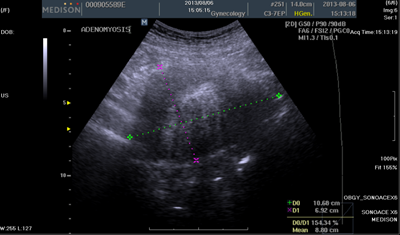

The method of intervention II was to first identify her greatest stressor and then let go of it, followed by intensive practice of mantra meditation, mindfulness meditation, and MBSR exercises, for approximately 4hours per day and approximately 28hours per week, while taking anti-inflammatory, haemostatic drugs, iron and vitamin B as necessary. The exercises of MBSR she did included mindfulness meditation, mind full breathing and body scan indoors, and mindful walking, mindful stretching in a large park with many big trees and beautiful lawn. Moreover, she practiced mindfulness in daily activities, paying attention to the present rather than the past or future, focusing on bodily sensations and movements and observing her thoughts none judgmentally. After 1.5month, her symptoms had markedly alleviated. The serum CA125 level, menstrual bleeding, and menstrual pain at this time are shown in Figure 2. The ultrasound graph is shown as Figure 4. The patient continued with the same meditation activities afterward, practicing approximately 2.5hours a day (for a total of about 17.5hours per week), and continued taking the same medication as necessary. Her symptoms had further improved as shown in Figure 2. In 2014, the patient had a large amount of menstrual bleeding in June, rare bleeding in July, and none in August. Her menopause was accurately diagnosed in December 2014. She had low-level bleeding twice in 2015, and non in 2016.